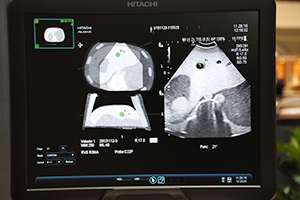

“3D Sim-Navigator”(FDA未承認)は,CTやMRIなどのボリュームデータを取り込み,超音波画面と同一断面のMPR画像をリアルタイムに同期表示する技術“RVS”の新しいアプリケーションである。バイポーラ電極針によるRFAにおいて,2D/3D画像の表示や針間距離の計測により,電極針穿刺のシミュレーションとナビゲーションを可能にする。

複数電極針穿刺を支援する“3D Sim-Navigator” |